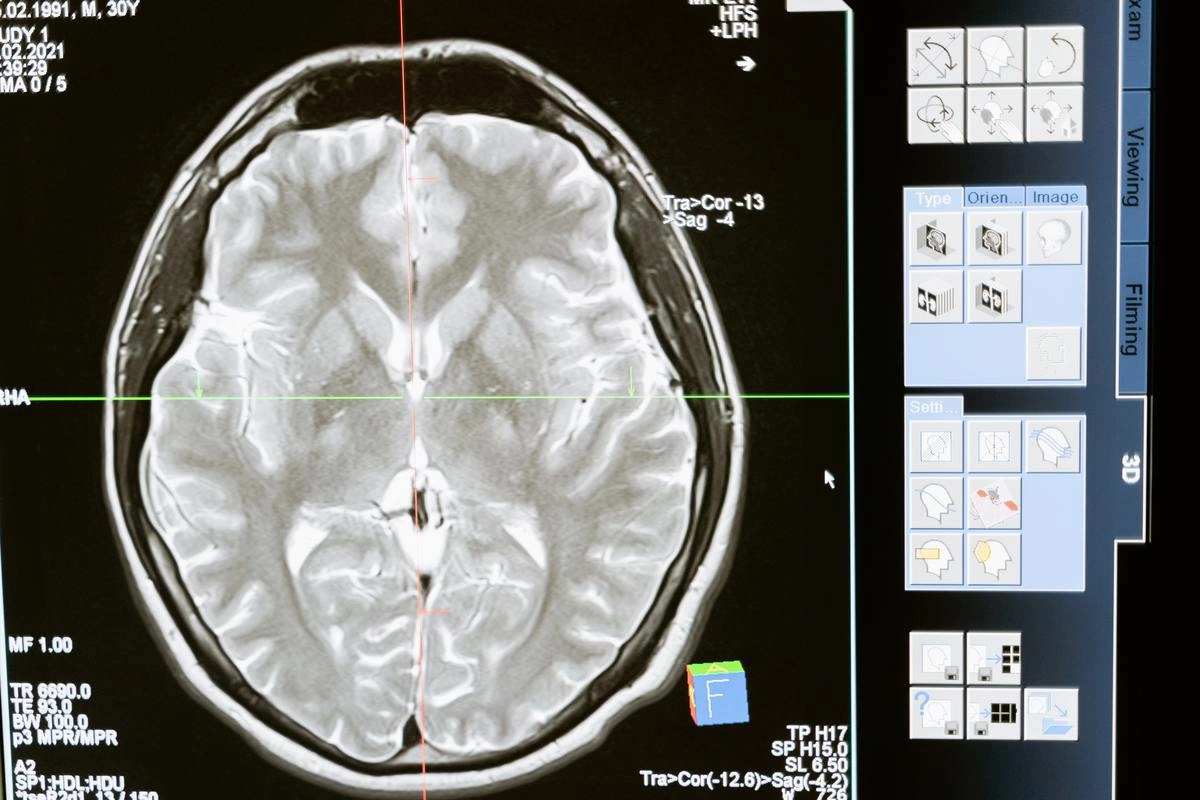

Согласно новому исследованию ученых из Орхусского университета (Дания) у людей, страдающих расстройством поведения во время быстрого сна (RBD), нарушается кровоток в головном мозге, что приводит к нехватке кислорода в ткани мозга. В долгосрочной перспективе это может вызвать симптомы болезни Паркинсона.

Результаты исследования, опубликованные в журнале Brain, показали, что у пациентов с нарушением сна был ухудшенный кровотока в коре головного мозга и в мелких кровеносных сосудах. Изменения в головном мозге связаны с уменьшением количества нейротрансмиттеров и ухудшением когнитивных функций.